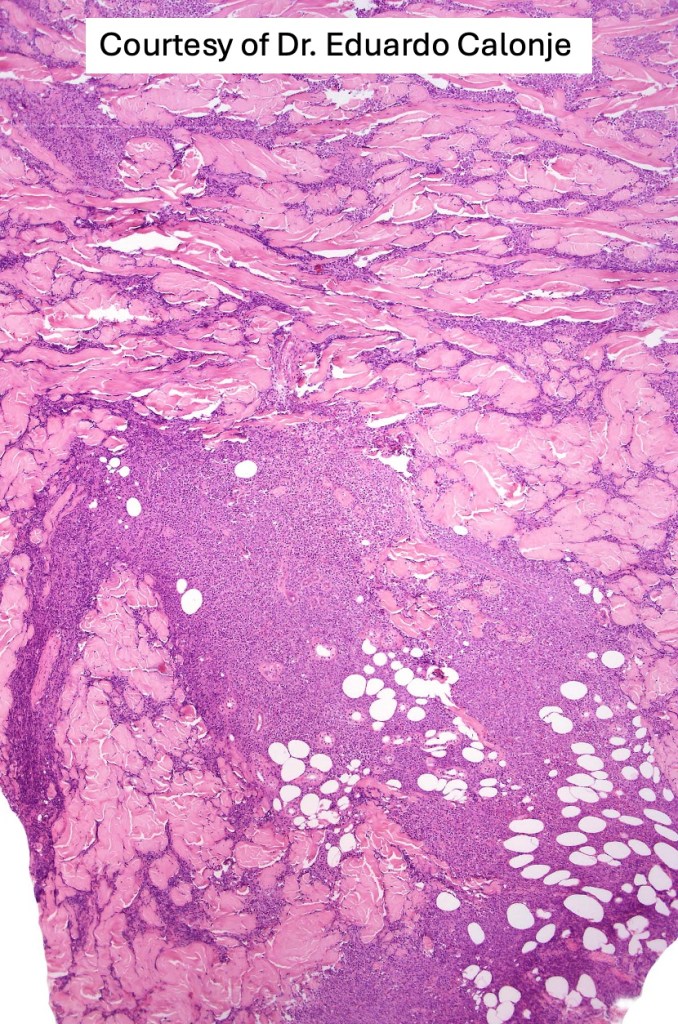

. Dermal +/- subcutaneous fat infiltrate

. No angioinvasion or angiodestruction

. Monotonous blast cells with gray-blue cytoplasm & irrregular vesicular nuclei with prominent nucleoli